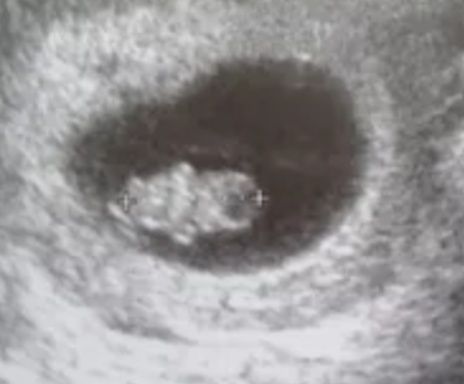

Лучше в следующий раз возьмите. На 21 день вам покажут кружочек и скажут, что это плодное яйцо. А в следующий раз когда переназначат, там уже целый человечек будет)) Изображение

Мой на все узи ходил. На 21 дпп было слышно сердцебиение

Аленка, у нас на 6 неделе на узи был на каспера похож - плодное яйцо по форме как перевернутая капля и как два глаза эмбрион и желточный мешок😄